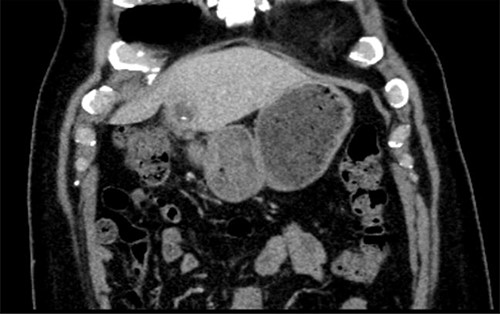

A 56-year-old man presented with a 2-day history of epigastric pain, leucocytosis and raised C Reactive Protein (CRP). A computed tomography (CT) scan revealed evidence of a 4.2 × 2.5 cm abscess in the left lobe of the liver (Segment III), with a linear radio-dense foreign body seen within the collection (Fig. 1). There was fat stranding around the pylorus. The patient was treated with antibiotics in his local hospital and a trial of aspiration revealed purulent fluid. An oesphagoduodenoscopy (OGD) was normal with no evidence of foreign body or inflammation in the stomach.